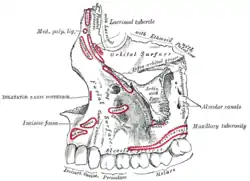

On the maxilla, the alveolar process is a ridge on the inferior surface, making up the thickest part of the bone. On the mandible it is a ridge on the superior surface. The structures hold the teeth and are encased by gums as part of the oral cavity.[11] Congruent with much of the mandibular canal, the alveolar process comprises cells, nerves, blood vessels, lymphatic vessels, and periosteum.[8] The alveolar crest terminates uniformly at about the neck of the teeth (within about 1 to 2 mm in a healthy specimen).[12][13]

Superior area of the alveolar process on the mandible The alveolar process of the maxilla is located at its inferior surface.

The alveolar process of the maxilla is located at its inferior surface. 3D animation showing placement of teeth in human skull